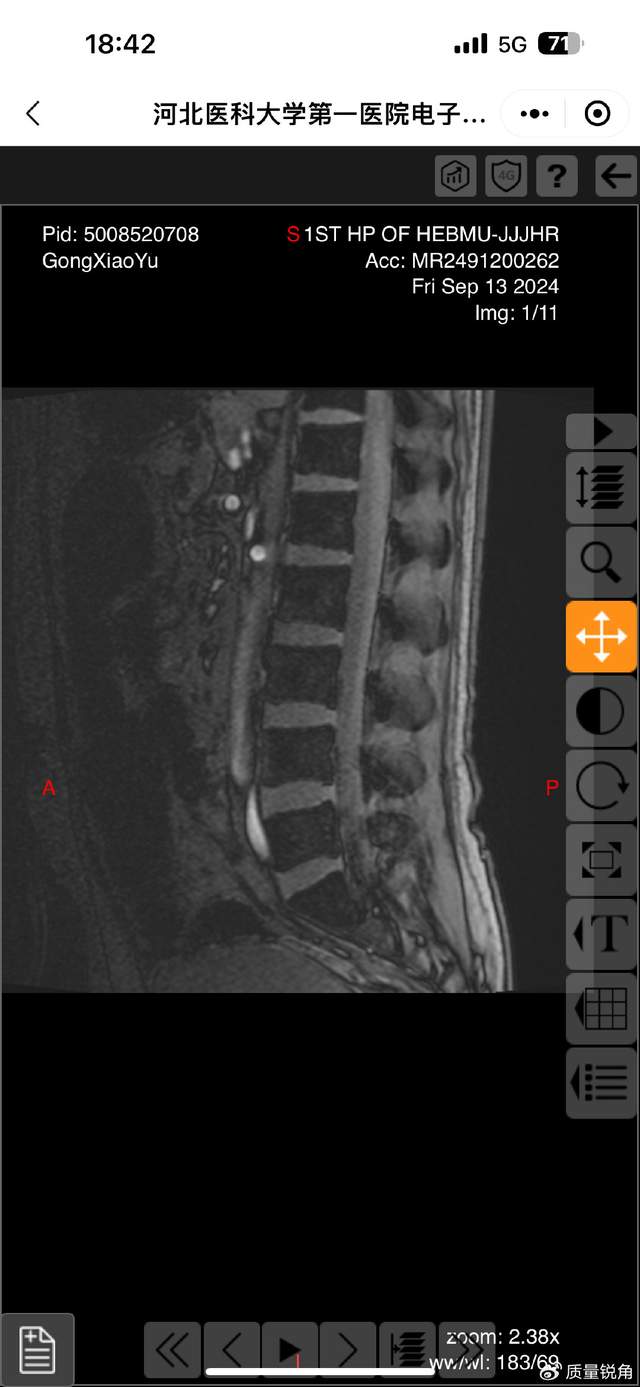

这起纠纷的源头是一场普通交通事故。原告龚小玉诉称,事故导致自己颈椎、腰骶骨折,向法院提交了病历、司法鉴定报告等证据,主张赔偿。但叶某团队手中,却持有龚小玉事发后发送的医疗影像资料。“我们找了三位骨科专家会诊,影像里只有骨质增生,没有任何新鲜或陈旧骨折的痕迹。”叶某表示,一审、二审中,他们多次提交该影像证据,并当庭请求法院责令龚小玉出示原始骨折影像——这是人身损害赔偿案件中证明伤情的核心直接证据。

可关键是,龚某玉之前发给叶某他们手里的医疗影像清清楚楚,只有骨质增生,压根没骨折啊!二审时找医生看CT,医生也说“看不清”骨折痕迹,叶某他们还向石家庄市中级法院说了,只要龚某玉拿出真实骨折影像,立马无条件赔偿,结果法院根本不理!